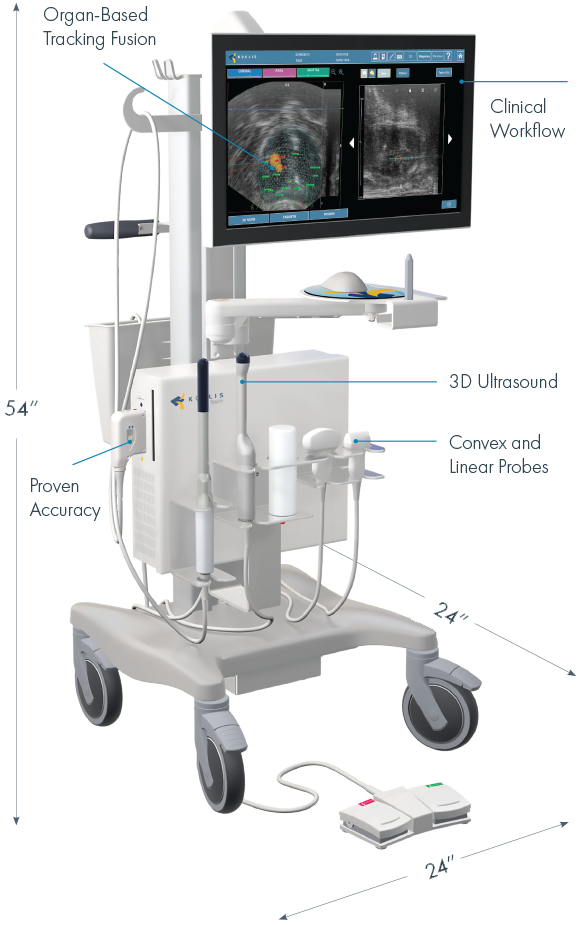

Ultra Compact Versatile Platform

- MRI/US fusion prostate biopsy

- PET/US fusion prostate biopsy

- Ultrasound guided prostate biopsy

KOELIS Trinity® facilitates a range of other procedures including:

Rectal spacer placement

Fiducial marker insertion

Ablative therapy planning & guidance for prostate cancer

Diagnostic transrectal, abdominal, and small parts ultrasound